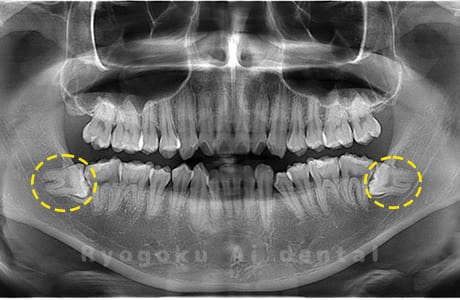

水平埋伏の親知らず

歯茎の中で完全に横に生えてしまうタイプです。

この親知らずを水平埋伏智歯と言います。このタイプはほとんどが下顎のケースです。真横に生えているので抜歯の際は難易度が高く2~3つに砕いて分けて抜歯をします。